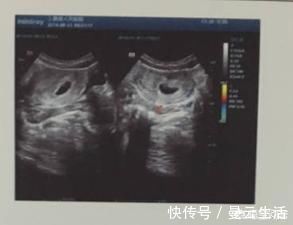

孕早期需要在B超下查看孕囊的位置、大小、形态,以排除空孕囊、假孕囊。也就是说看见孕囊了不代表就正常怀孕了,也可能是怀了个假孕。

四、确认胚胎个数

确认怀的是单胎还是双胎、多胎。